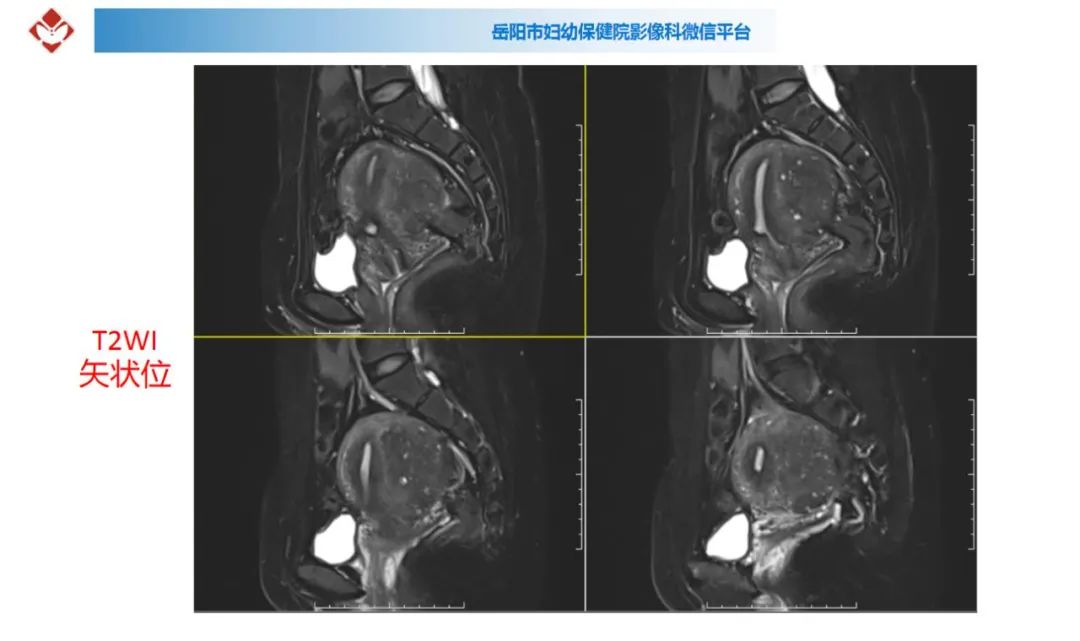

典型疑难病例讨论

来源:岳阳市妇幼保健院影像科